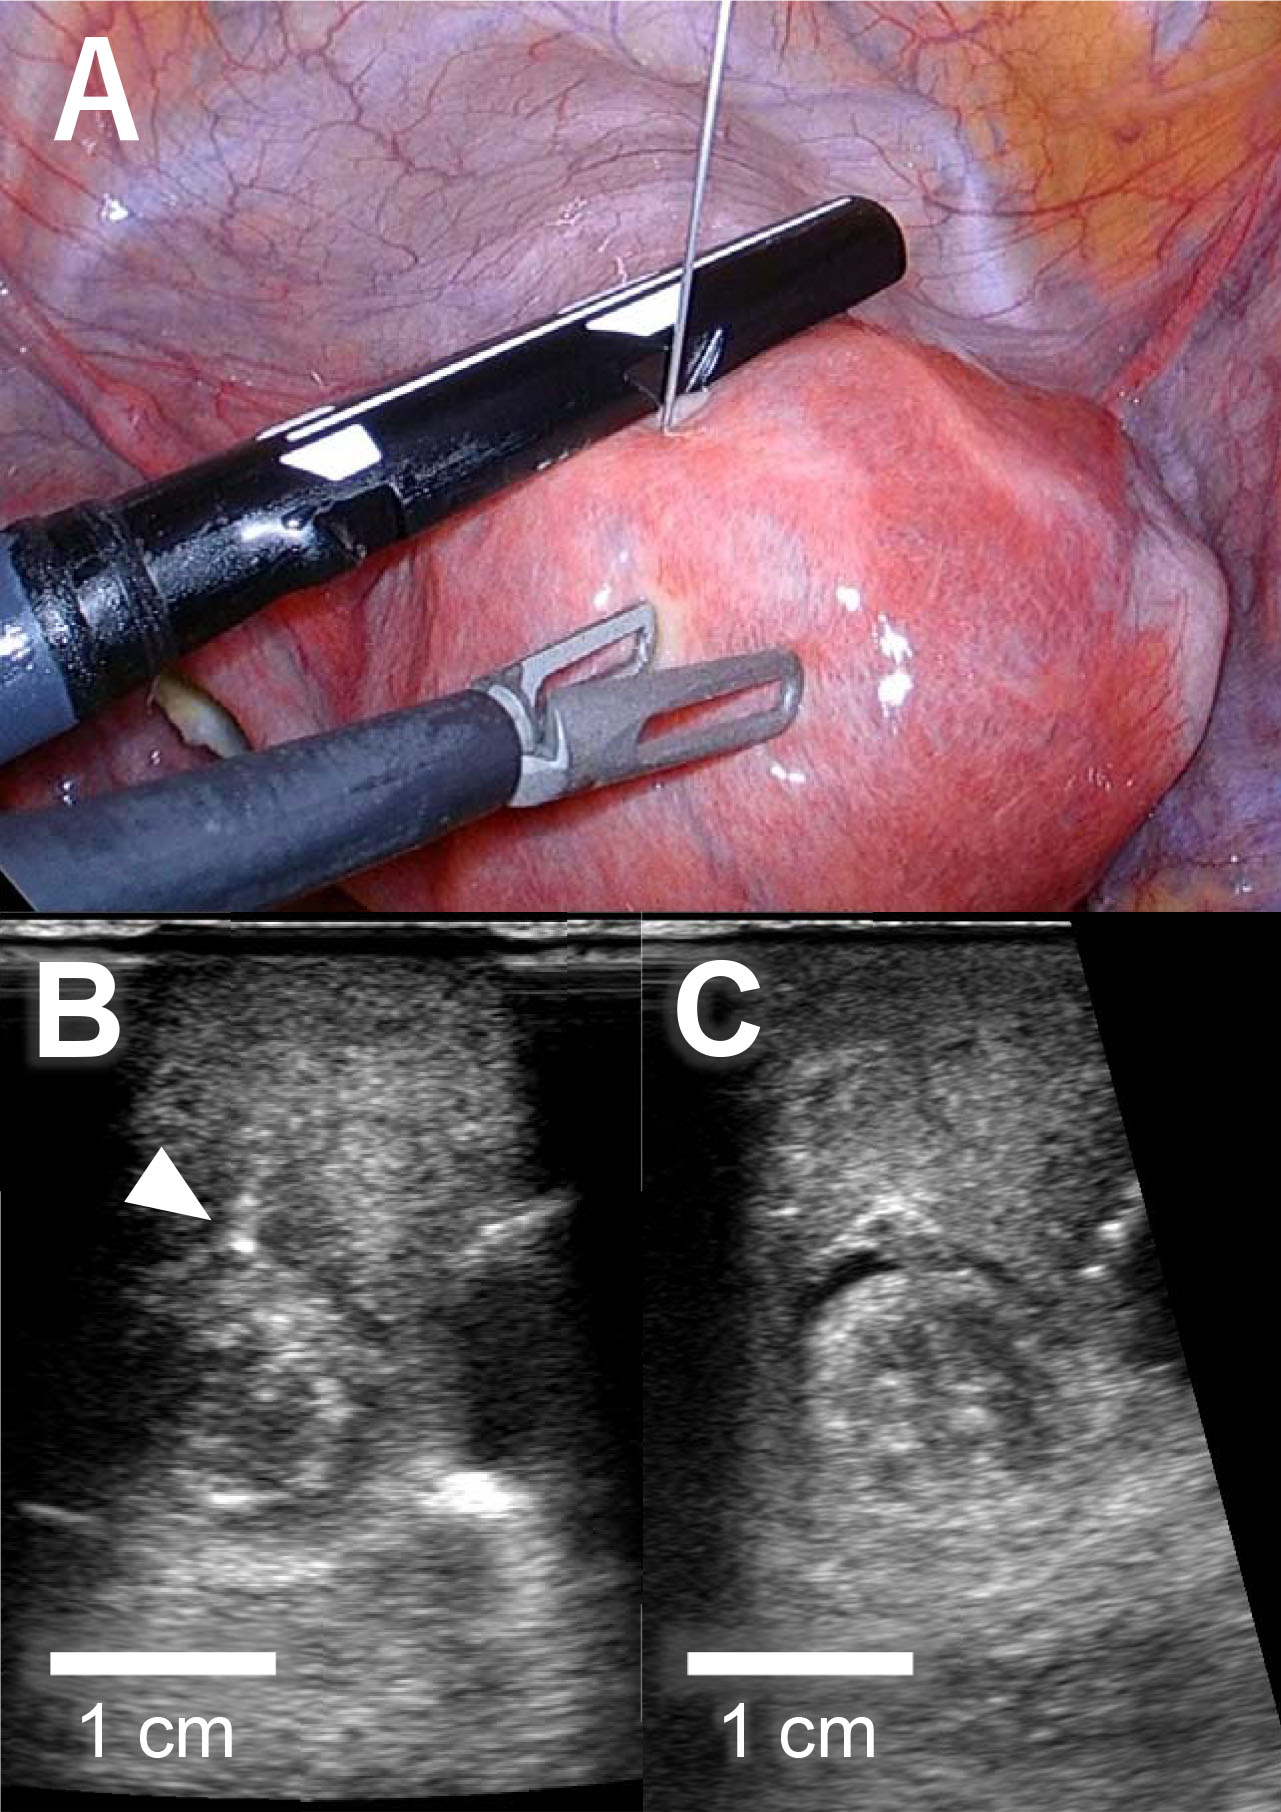

A 36-year-old nulligravida woman visited our clinic for an evaluation of her infertility. She was healthy, and her menses were regular and normal. Transvaginal ultrasonography revealed a type 2 submucosal myoma with a 60% myometrial extension measuring 15 mm in the anterior uterine wall and a type 4 intramural myoma (classified via guidelines from the International Federation of Gynecology and Obstetrics) measuring 49 mm in the posterior uterine wall. Magnetic resonance imaging suggested that the posterior myoma was a cellular leiomyoma (Fig. 1A). To make a definitive diagnosis regarding the intramural myoma, we planned a laparoscopic myomectomy. Furthermore, we planned to laparoscopically resect the submucosal myoma considering the myoma’s negative effect on implantation. Since the submucosal myoma was not visible from the external side of the uterus, we planned to use LUS to detect it. The location of the submucosal myoma was preoperatively assessed by transvaginal ultrasound sonography and magnetic resonance imaging. We measured the depth from the external side and the distance from the midline and fundus of the uterus. During the surgery, we used an ultrasound machine (Aplio a verifia CUS-AA000, Canon Medical Systems, Otawara, Tochigi, Japan) and a transducer (Linear array transducer PET-805LA, Canon Medical Systems, Otawara, Tochigi, Japan) with the detection frequency set at 7.0 MHz. We inserted the transducer through a 12-mm trocar (Fig. 1B). The submucosal myoma was visualized successfully with LUS immediately after the transducer was placed on the anticipated area of the anterior wall. Vasopressin (2 units diluted in 10 mL of saline) was injected precisely between the myoma and the myometrium under ultrasonography guidance (Fig. 2A,B). LUS also confirmed that the injected vasopressin effectively spread between the myoma and the myometrium (Fig. 2C). Using laparoscopic forceps and monopolar cautery, both the submucosal and the intramural myomas were successfully removed from the uterus without breaching the endometrium (Fig. 3A,B). The myomas were morcellated in a bag so that small fragments would not be scattered into the peritoneal cavity. The myoma beds were sutured to double to triple-layer closure with absorbable surgical thread. The postoperative course was uneventful, and the patient was discharged from the hospital as scheduled. No abnormal signs were detected at hospital visits 1 and 3 months after the surgery, and the initiation of fertility treatment was planned for 6 months after the surgery.

Fig. 1.Images of submucosal and intramural myomas. (A) Magnetic resonance image of the uterus. The submucosal myoma (*) in the anterior wall of the uterus was 40% intramural. The intramural myoma (†) in the posterior wall of the uterus was suggested as a cellular leiomyoma. (B) Image of laparoscopic ultrasonography during laparoscopic surgery. Transducer put on the anterior wall of the uterus, as shown in Fig. 2A, with a submucosal myoma (*) and an intramural myoma (†) clearly shown. A uterine manipulator is indicated by ‡. The schematic diagram at the bottom right explains the image of ultrasonography.